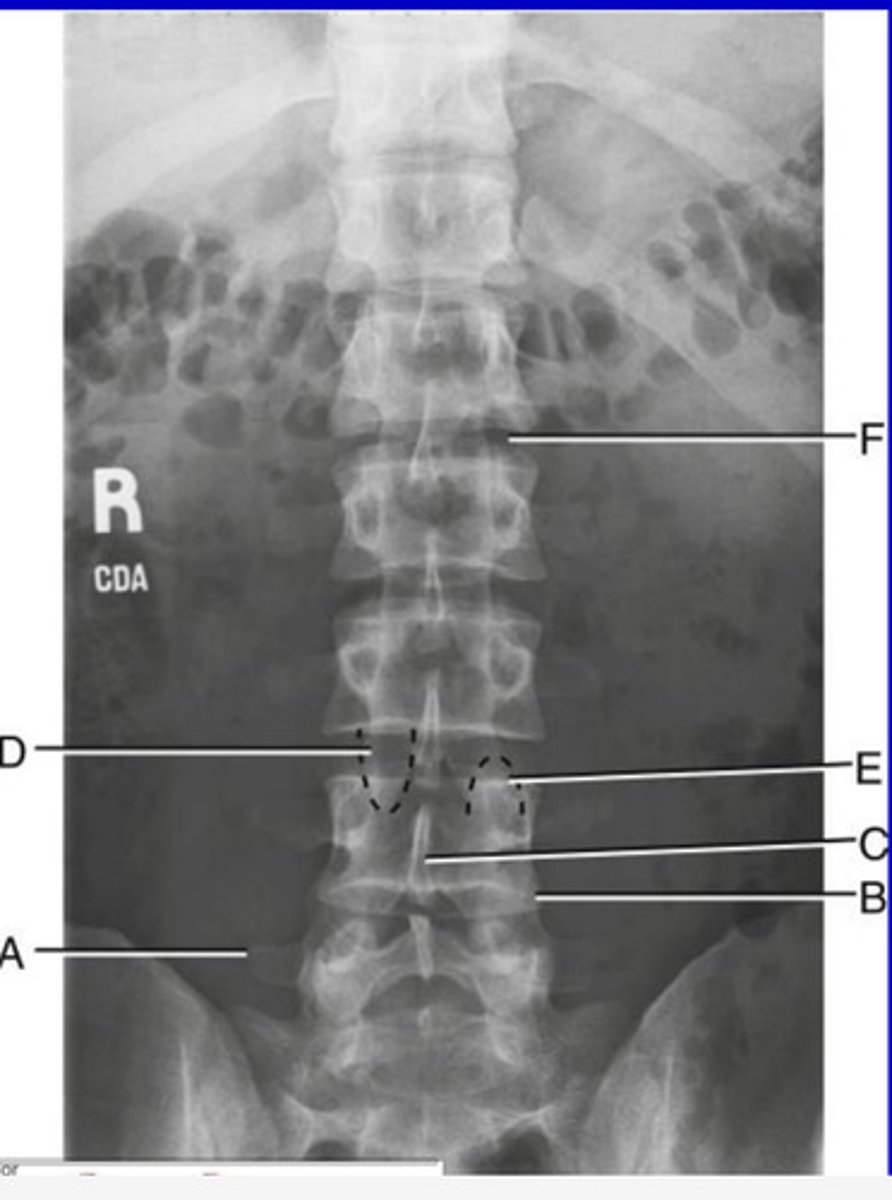

R sacroiliac joint

A.

L1 transverse process

B.

L2 spinous process

C.

L3-4 intervertebral space

D.

Ala of sacrum

E.

AP L spine

What position?